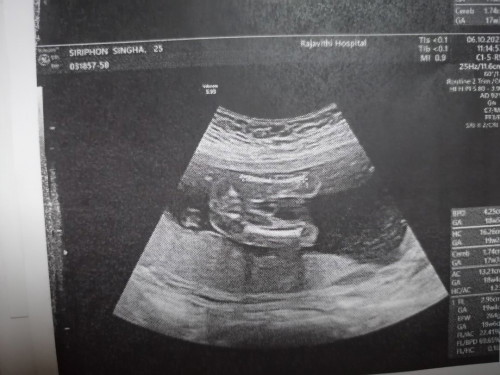

เพศลูกในครรภ์

อยากทราบว่าผู้หญิงหรือผู้ชายคะแต่หมอบอกผู้หญิงซาวตอน 20วีค+

แบบนี้หญิงหรือชายค่ะ😂

เป็นกลีบชัด ผญ.ค่ะแม่

ท่าเดียวกันเลยค่ะ ผญ

ผู้หญิงค่ะ

น่าจะผู้หญิงนะคะ

น่าจะหญิงค่ะ

ไม่มีกะจู๋😁